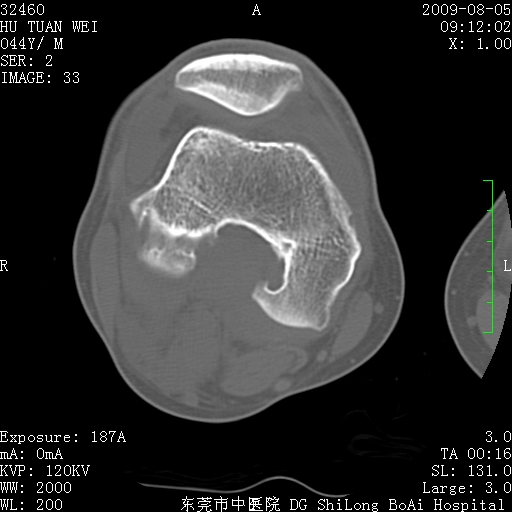

中年男性,膝韧带损伤术前检查!其他病史不清粗,不是我接手病人、且出院了!

1、股骨下段囊状膨胀性病变,边缘硬化明显,内多个残留骨棘呈多房型改变,囊腔密度较高无钙化,膝关节滑膜囊增厚,密度增高,关节腔少量积液。考虑:邻关节囊肿、退变性囊肿(软骨下囊肿)、着色性绒毛结节性滑膜炎、abc、骨巨、良性纤维组织细胞瘤等鉴。虽然年龄偏大,部位于骨端,但有外伤史,本人还是倾向于动脉瘤样骨囊肿(abc)可能性大。邻关节囊肿及软骨下囊肿次之考虑。

2、胫骨髁间棘撕脱骨折,交叉韧带损伤可能;

3、关节退行性改变。

病理结果:色素沉着绒毛结节性滑膜炎

感谢反馈病理结果!本病为慢性关节病变。以关节滑膜高度增生、绒毛结节形成伴含铁血黄素趁着为特点。病因:有炎症、肿瘤、外伤关节出血、代谢障碍、变态反应及感染等学说。增强扫描呈关节腔内单个或多个强化的软组织结节影或滑膜不规则增厚伴关节积液为本病的特征性表现。